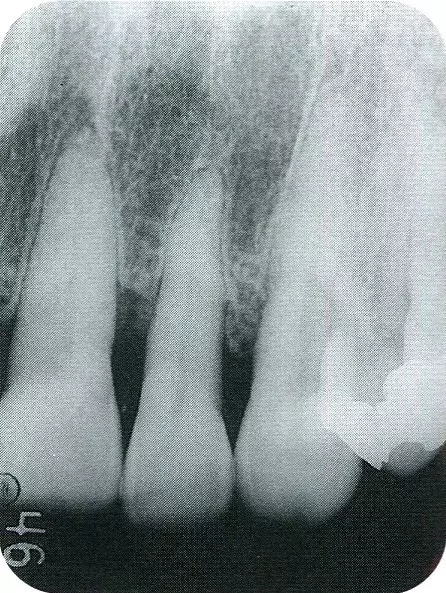

640.webp (1).jpg

▲圖7-2  術(shù)前x片。確認(rèn)存在垂直性深骨缺損。